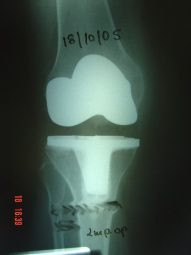

Artrosis de rodilla derecha por valgo severo

Envíado por Dr. Ricardo Antonio Gómez G.